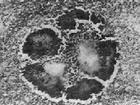

頜面部放線菌病

628健康網(wǎng)為您分享有關(guān)頜面部放線菌病的癥狀,頜面部放線菌病的治療方法,頜面部放線菌病的預(yù)防知識(shí),頜面部放線菌病的癥狀...